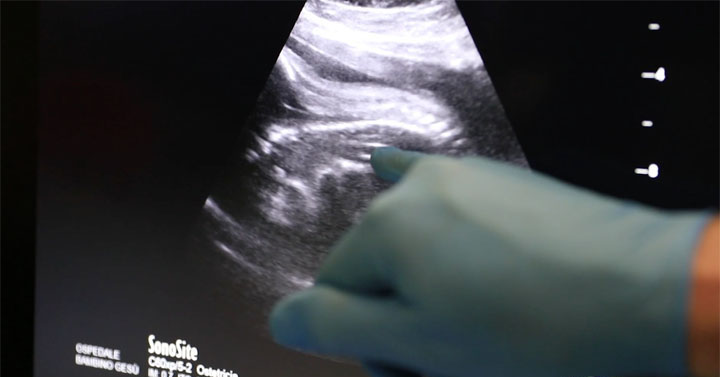

Con la mamma in anestesia locale ed il feto “sedato” con una puntura sulla coscia, è stato inserito un fetoscopio (sonda molto sottile dotata di telecamera a fibre ottiche) nell’addome della gestante. Passando per la bocca del feto (lungo appena 35cm per 1,2kg di peso), è stata raggiunta la trachea dove è stato posizionato e gonfiato un minuscolo palloncino, un “tappo” che blocca la fuoriuscita del liquido normalmente prodotto dal polmone. L’accumulo del fluido all’interno dei polmoni, che nei casi di ernia diaframmatica sono di dimensioni ridotte, li mantiene in espansione e ne favorisce lo sviluppo. Circa un mese prima del parto, il palloncino sarà rimosso con la stessa procedura per permettere al neonato di avere la trachea libera e quindi di respirare normalmente al momento della nascita. A distanza di 10 giorni dall’intervento, i controlli ecografici hanno rilevato un significativo aumento del volume dei polmoni fetali.